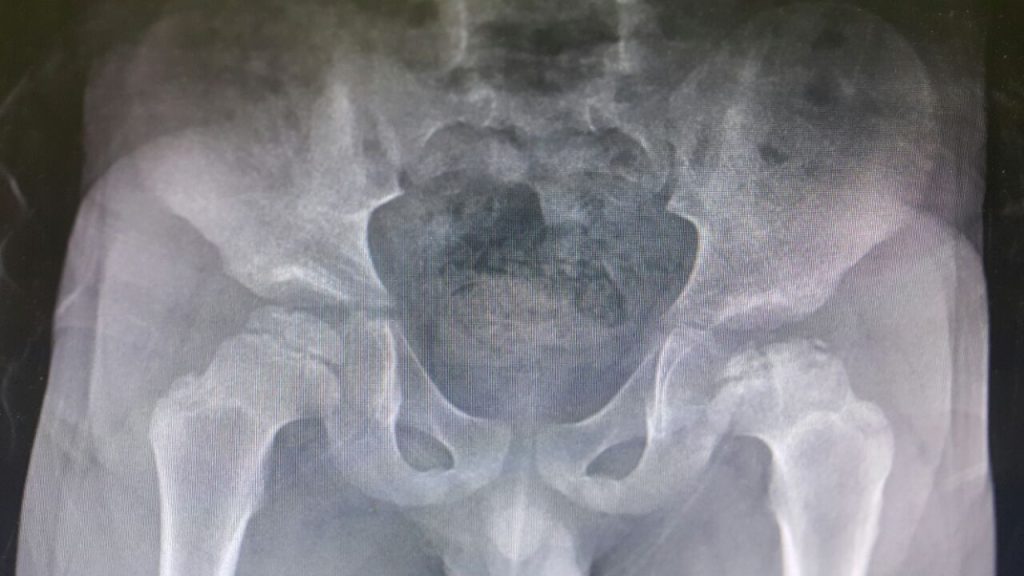

Kalça Çıkığı

KALÇA ÇIKIĞI Amaç: Toplumumuzu gelişimsel kalça çıkığı ve kalçaların normal gelişimi konusunda bilgilendirmek. Gelişimsel Kalça Çıkığı ve Kalça Gelişim Bozukluğu Nedir? Kalça çıkığı, eklemi oluşturan uyluk […]